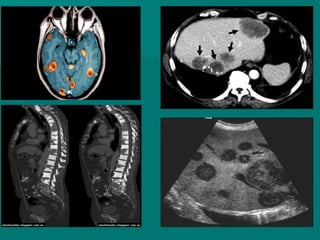

Metástasis

Cuando afecta a otras zonas del cuerpo: tejido blando (como el tejido de

la mama opuesta, ganglios linfáticos lejanos o piel), órganos como el

hígado o los pulmones y los huesos.